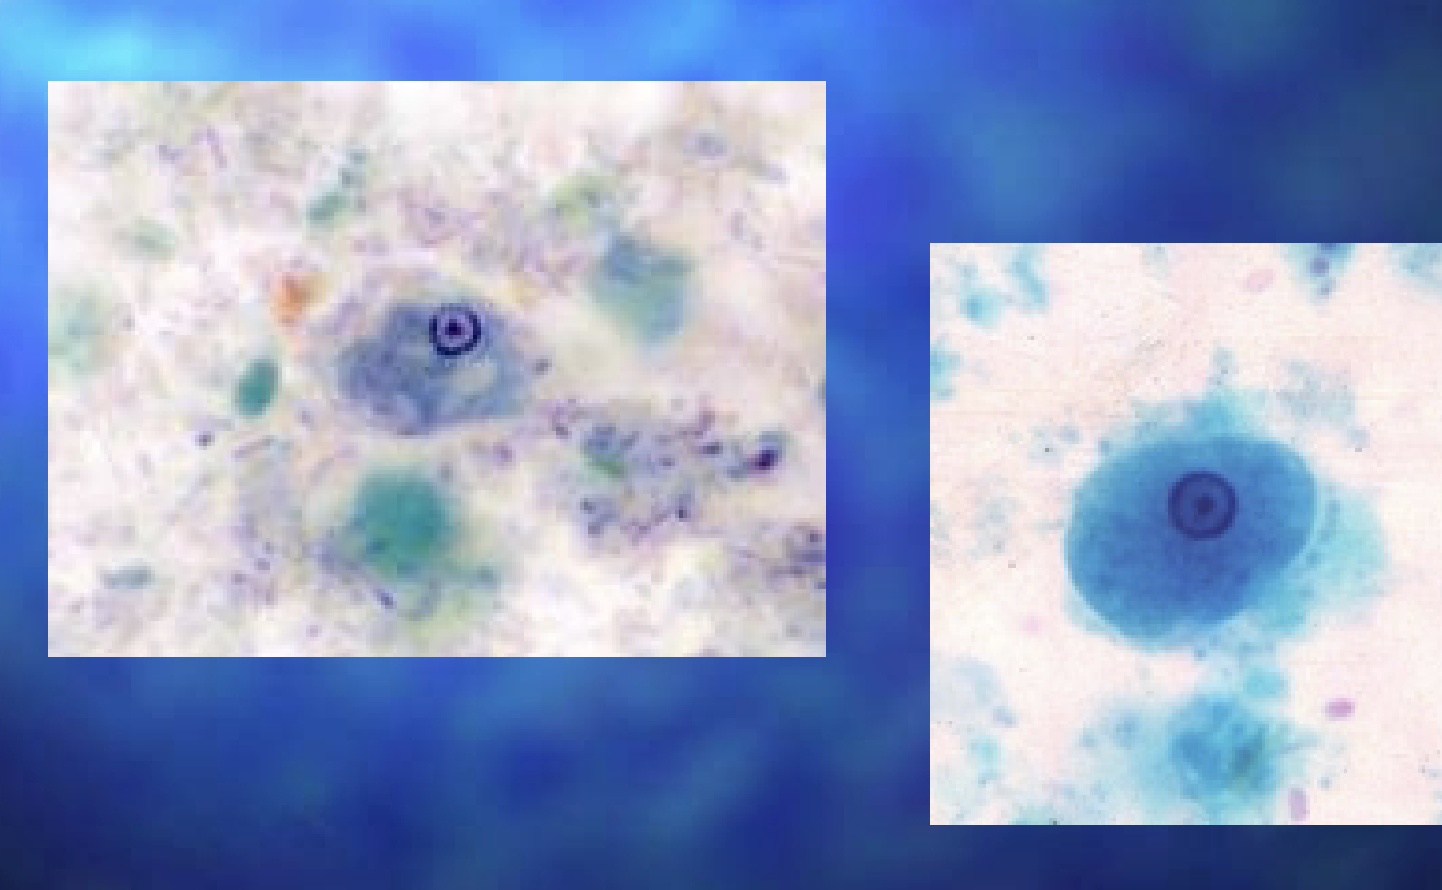

Entamoeba histolytica troph

Entamoeba histolytica troph

Naegleria fowleri

Naegleria fowleri

Naegleria fowleri cyst